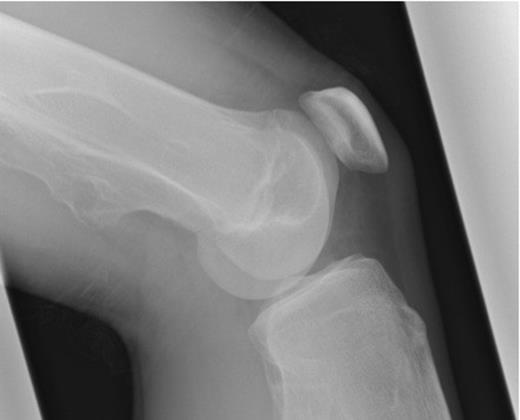

He presented to his local orthopaedic department where repeated radiographs (Figure 1) illustrated decreased cortical definition of the exostosis arising from the medial femoral metaphysis 15cm above the knee joint. There was no periosteal reaction but there was evidence of adjacent soft tissue swelling. At this point he was referred to the regional sarcoma MDT due to concern that the lesion had undergone malignant transformation.